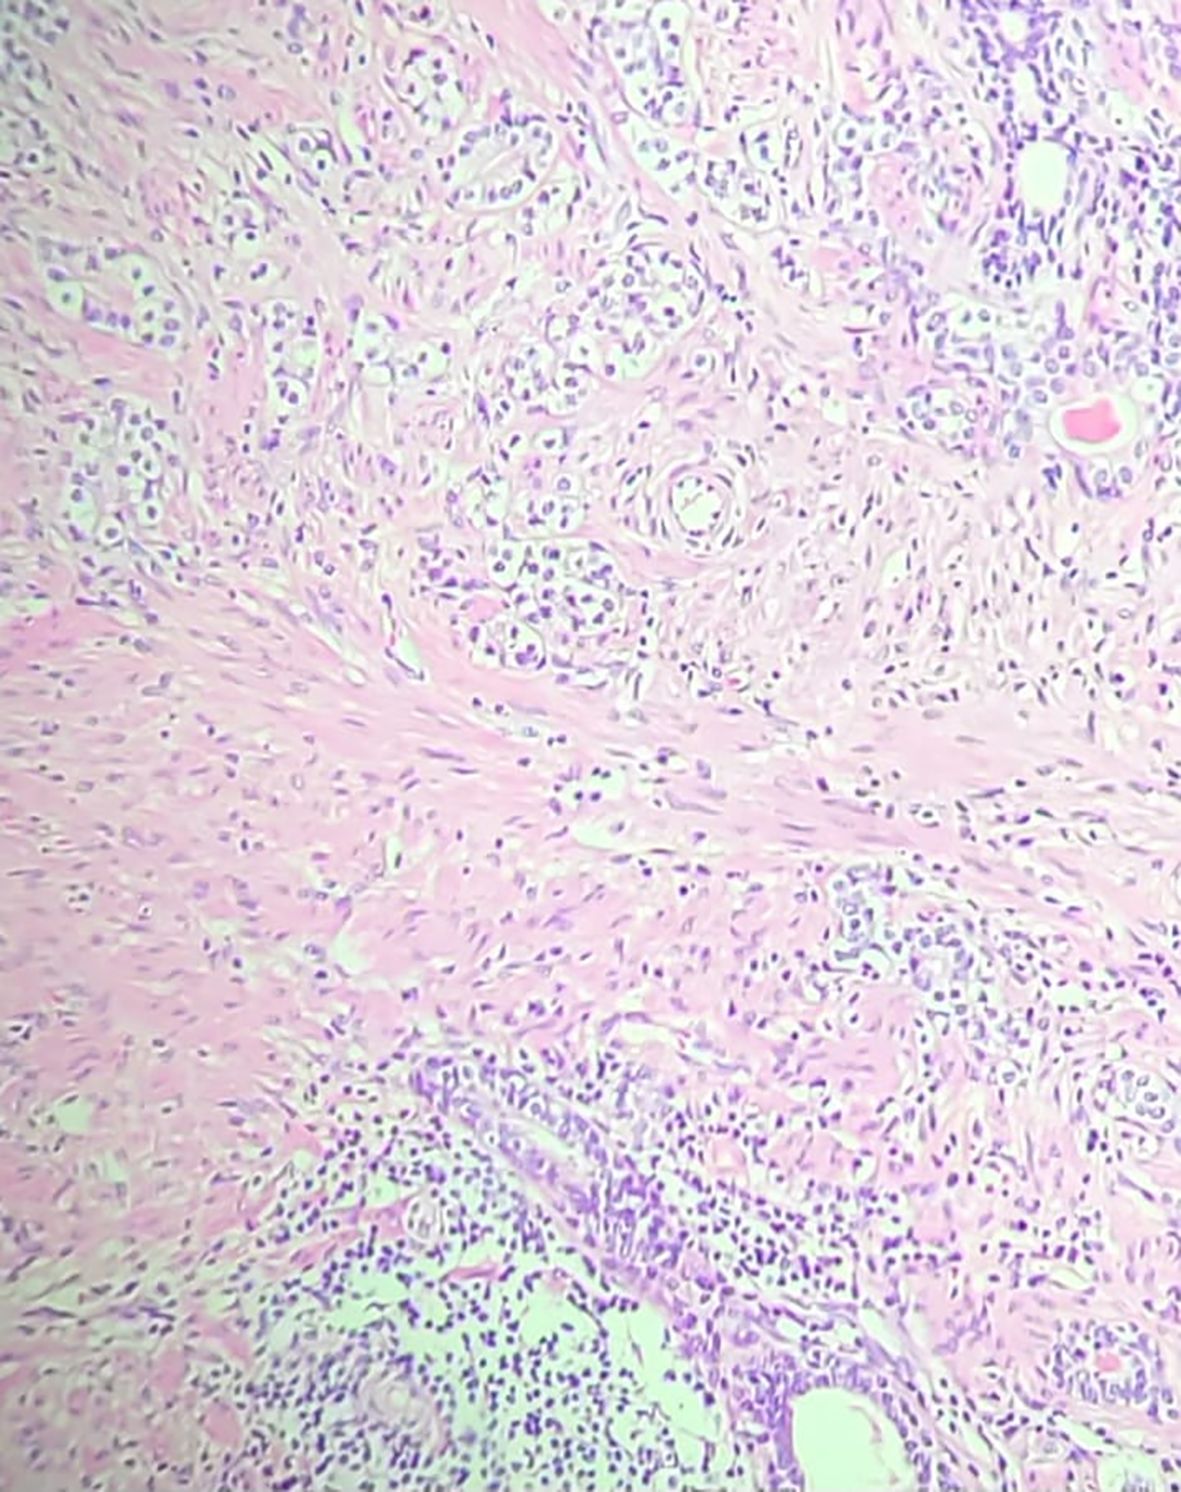

The patient underwent neoadjuvant therapy with ADT plus a novel hormonal agent from April 14 to October 15, 2024, resulting in significant tumor shrinkage. He subsequently underwent radical prostatectomy on November 1, 2024. Surgical pathology revealed a residual 9 mm acinar adenocarcinoma focus with perineural invasion, but no vascular invasion. Surgical margins, seminal vesicles, and deferent ducts were negative. Background findings included basal cell hyperplasia, acinar atrophy, mild lymphohistiocytic inflammation, and stromal remodeling. Molecular testing confirmed a TMPRSS2::ERG fusion and PTEN loss (Figure 3).

Hematoxylin–eosin (H&E) stained prostate section at 20× magnification. The field shows crowded, irregular acinar structures with enlarged, hyperchromatic nuclei and prominent nucleoli, consistent with acinar adenocarcinoma. Surrounding pink fibromuscular stroma contains lymphohistiocytic inflammatory infiltrates, illustrating adjacent chronic prostatitis-type changes. Coloration is typical of H&E: purple nuclei and pink cytoplasm/stroma. The architectural distortion and glandular crowding contrast with nearby benign-appearing glands. This microscopic image corresponds to the tumor area identified on MRI and biopsy, providing histologic confirmation of carcinoma with neighboring inflammation.

Figure 3. Hematoxylin and Eosin (H&E) stained section (20× magnification) from the radical prostatectomy specimen, demonstrating acinar adenocarcinoma with Gleason score 7 (3 + 4), ISUP grade group 2. Adjacent areas showed chronic inflammatory infiltrates consistent with prostatitis, supporting the hypothesis that COVID-19–related inflammation may have contributed to carcinogenesis in this patient.